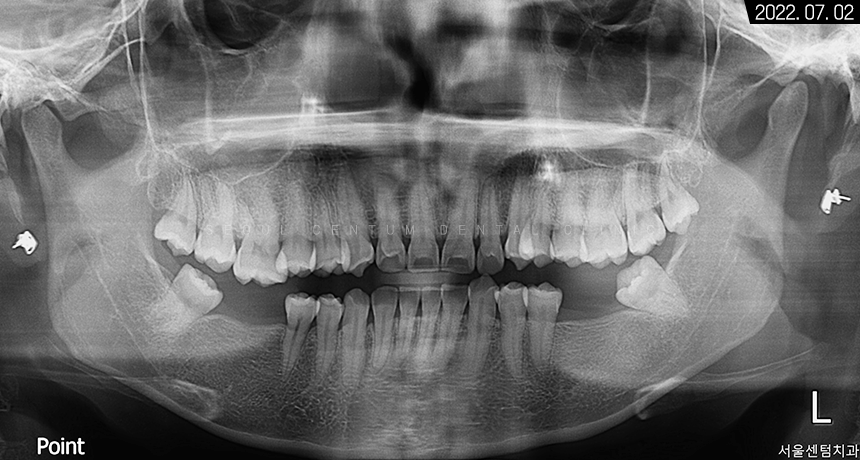

그래서 우선 파노라마 엑스레이 촬영으로

전체적인 구강 환경을 살펴봤는데요.

전치부는 과잉 밀집으로 몰려있는 것이 보였고

위턱은 사랑니까지 맹출 되어

아주 빽빽한 치열을 갖고 계셨습니다.

아래턱은 어금니 상실 부위가 여러 군데여서

식사가 불편하셨을 것으로 예상되었습니다.